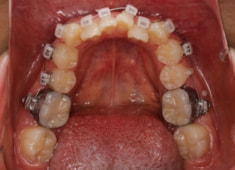

治療開始時